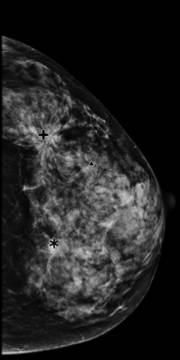

乳腺钼靶肿块判读